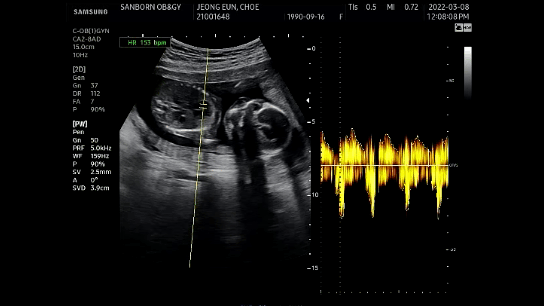

호띵이 심장박동

심장박동수는 153 BPM으로 우렁차게 심장이 뛰고 있다.